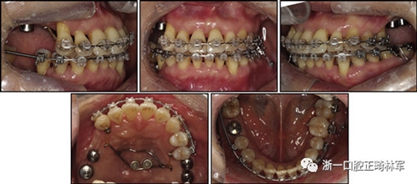

完成診斷性設(shè)計后,治療后穩(wěn)定的咬合是確定的(圖5)。進行治療之前,治療計劃和順序需要通過涉及正畸,牙周病和修復(fù)的多學(xué)科綜合治療方法加以確認(圖6)。牙周治療應(yīng)在正畸治療前完成。牙周疾病的治療采用全口潔治,上頜和下頜前牙區(qū)的刮治術(shù),以及下頜左側(cè)后牙區(qū)的翻瓣手術(shù)。休息3個月后,幾乎每個部位都實現(xiàn)了牙周袋深度縮小,探針出血幾乎沒有(表III)??刂蒲装Y后,開始正畸治療。在正畸治療期間定期進行牙周維護的復(fù)診檢查。

拔除下頜左側(cè)側(cè)切牙,除了4顆前牙外,下頜和上頜牙齒通過0.022英寸的Clippy-C裝置(日本東京的Tomy)粘接聯(lián)合。磨牙管粘結(jié)在下頜磨牙上。排齊過程從0.014英寸的鎳鈦弓絲開始,然后是0.016英寸的鎳鈦弓絲。為了美觀,在拔除的下頜左側(cè)側(cè)切牙間隙中放入一個修復(fù)體。為了防止牙齒的圓形轉(zhuǎn)動,4根上頜前牙被繞過,使牙齒能在尖牙被推向遠中后排齊。將兩個TADs(Orlus,Ortholution,Seoul,Korea)放置在腭板,并且有鉤子附著。將一小段0.016英寸的不銹鋼弓絲放置在上頜左側(cè)尖牙和前磨牙上,并且通過附著在腭板上的鉤子將上頜尖牙和左側(cè)前磨牙推向遠中。

對于近中傾斜和過度萌出的上頜右側(cè)尖牙,需要控制牙齒向遠中傾斜和向下推入。用兩個鉤子在兩側(cè)施加不同方向的力,以期望右側(cè)尖牙的推入(圖7)。在上頜尖牙遠中移動后,用一根0.014英寸的鎳鈦弓絲將4顆上頜前牙排齊。放置逐漸變硬的弓絲,直到上下兩個牙弓都放置0.017*0.025英寸的不銹鋼弓絲。然后關(guān)閉下頜前牙區(qū)間隙,用完全相同的力學(xué)原理將上頜全牙列向遠中移動,以獲得適當(dāng)?shù)母埠虾透采w。此外,還有一個0.017*0.025英寸β-鈦絲的直立彈簧應(yīng)用于下頜右側(cè)第二磨牙。當(dāng)直立彈簧接合到主弓絲上時,引起前磨牙的推入,第二磨牙的推出,前磨牙的頰側(cè)傾斜以及第二磨牙的舌側(cè)傾斜,以矯正牙弓形態(tài)(圖8)。

由于患者有多個缺失的后牙,因此考慮到具有垂直方向的喪失。然而,她在拔除后牙后立即去正畸科就診。她封閉了天然的左側(cè)前磨牙,并且沒有前牙的咬合磨損。因此,垂直維度被維持是確定的。在正畸治療過程中,牙種植體植入在上頜后牙區(qū)和下頜右側(cè)第一磨牙的位置(圖9)。經(jīng)過3個月的骨結(jié)合后,種植體用臨時冠修復(fù)以支持垂直維度。

圖9. 上頜牙齒推向遠中,糾正下頜左側(cè)磨牙的傾斜度,并放入種植體

在患者適應(yīng)了垂直維度和咬合后,裝置被去除(圖10)。主動治療時間為17個月。牙列立即用固定的保持器進行保持,保持器從下頜一側(cè)前磨牙到另一側(cè)前磨牙,以及從上頜一側(cè)前磨牙到另一側(cè)前磨牙的臨時牙冠上。此外,真空成型的保持器應(yīng)用于上下兩個牙弓。患者被轉(zhuǎn)診給修復(fù)??漆t(yī)生進行進一步的修復(fù)手術(shù),還轉(zhuǎn)診給牙周病專家進行維護和隨訪。在最終確認她的穩(wěn)定咬合和適應(yīng)后,進行最終修復(fù)體修復(fù)。